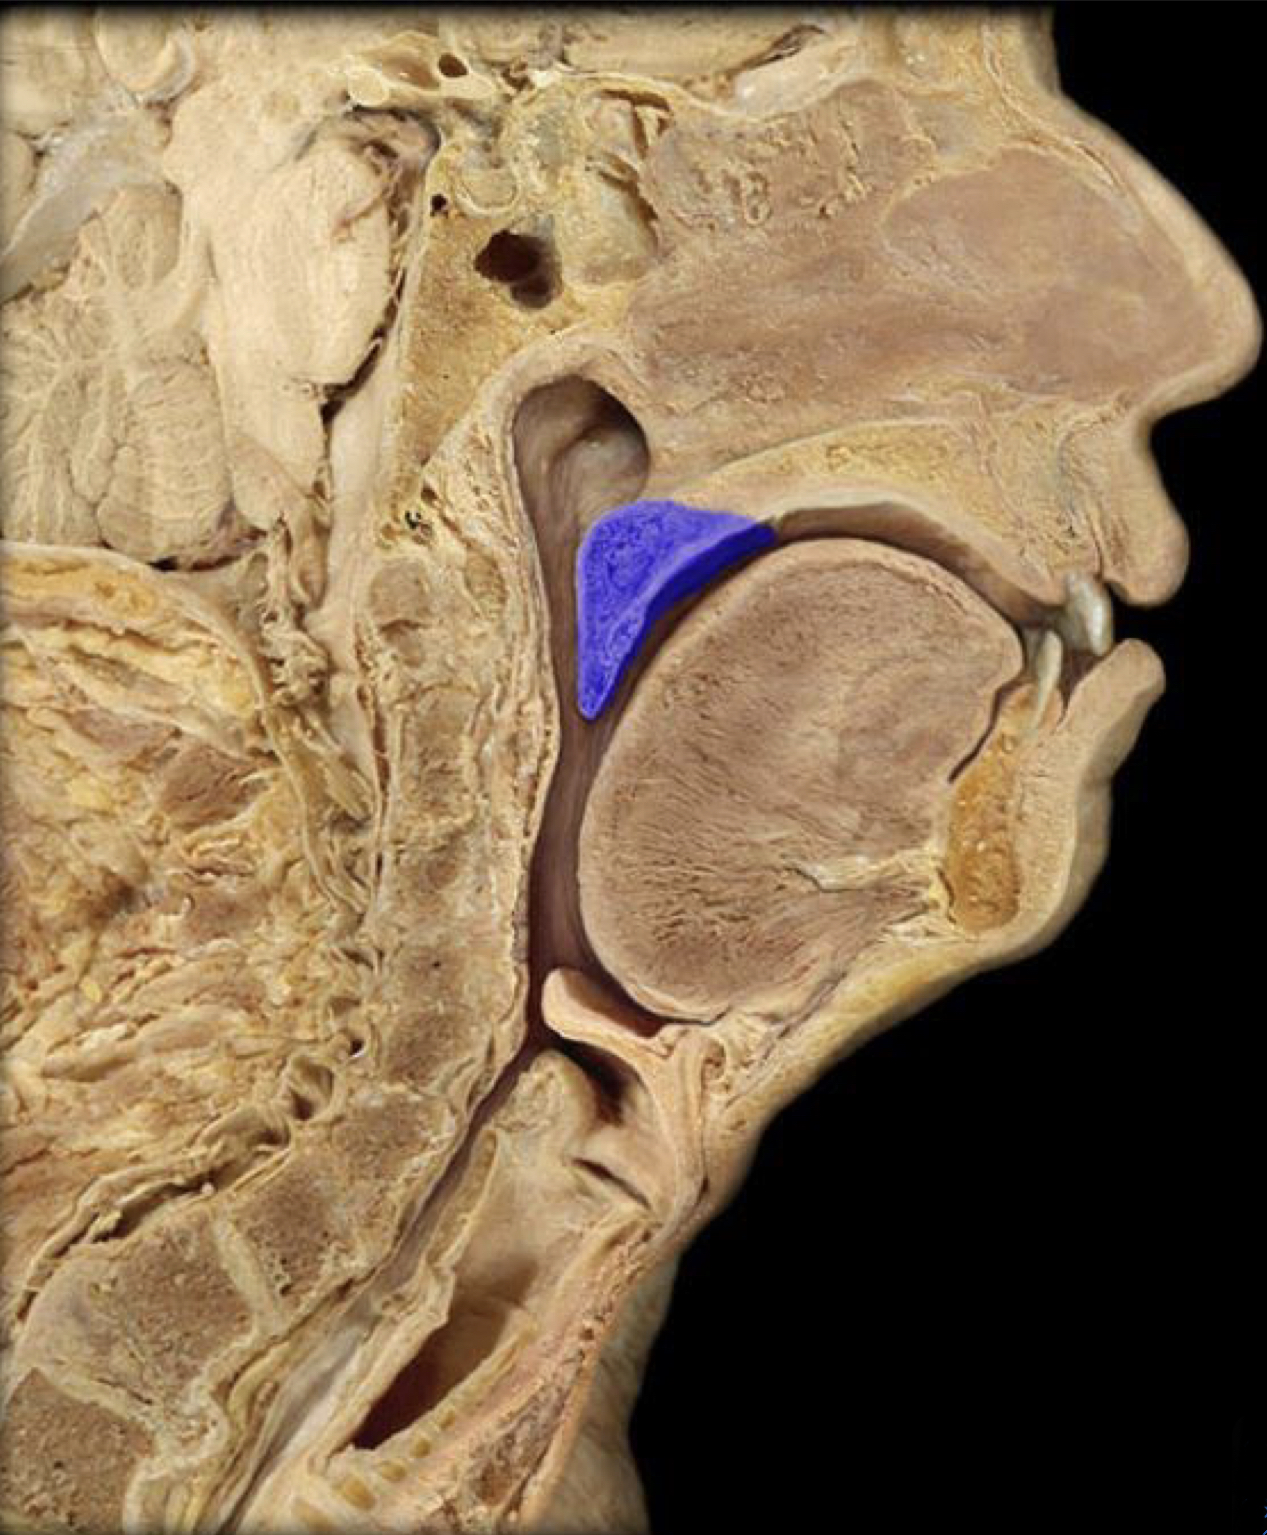

What structure is highlighted in blue?

Epiglottis